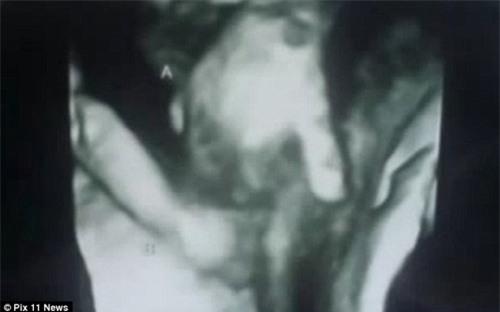

Thông tin này khiến cặp đôi vô cùng đau xót. Tuy nhiên, một hình ảnh khiến họ bất ngờ đó là dù thai nhi đã qua đời trong bụng mẹ nhưng bàn tay vẫn nắm chặt lấy tay của người chị song sinh.

Thai nhi đã chết vẫn nắm chặt tay chị song sinh.

Cặp đôi cũng đã lưu lại những hình ảnh siêu âm đặc biệt này như một kỷ vật để tưởng nhớ về bé Mason đã không may mắn qua đời trong bụng mẹ.